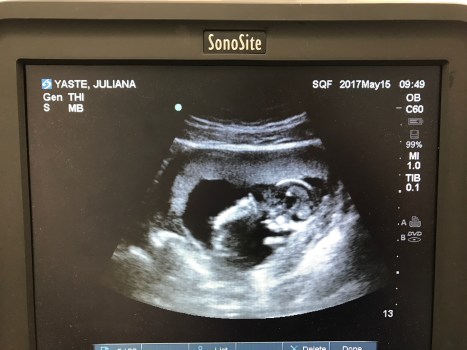

Every appointment when the doctor unveils my growing belly and douses it with jelly, I’m afraid that when his practiced hand comes down with the ultrasound wand my baby will have stopped developing, his heartbeat dormant, his life having eased away undetected. I imagine this every appointment, and often in between, preparing myself just in case. The weeks between each visit are a near constant stream of anxiety.

The doctor has finally stopped musing on fish and eggs and asked me to lie back. I pull up my shirt and he puts a paper blanket over my leggings, tucking it into the waist. The jelly comes out, and the wand lowers to my belly. I clench my jaw.

There he is. My baby. I can see his skeletal frame dancing in black and white on the ultrasound monitor. At the start he looked like a blob and now here he is, a tiny person.

“Alright, there he is, love,” says the doctor. He’s half talking to me, half to the instruments in front of him. He moves the wand around, taking measurements and muttering to himself. Finally he seems satisfied and turns his blue gaze to me.

“Everything looks just fine.”